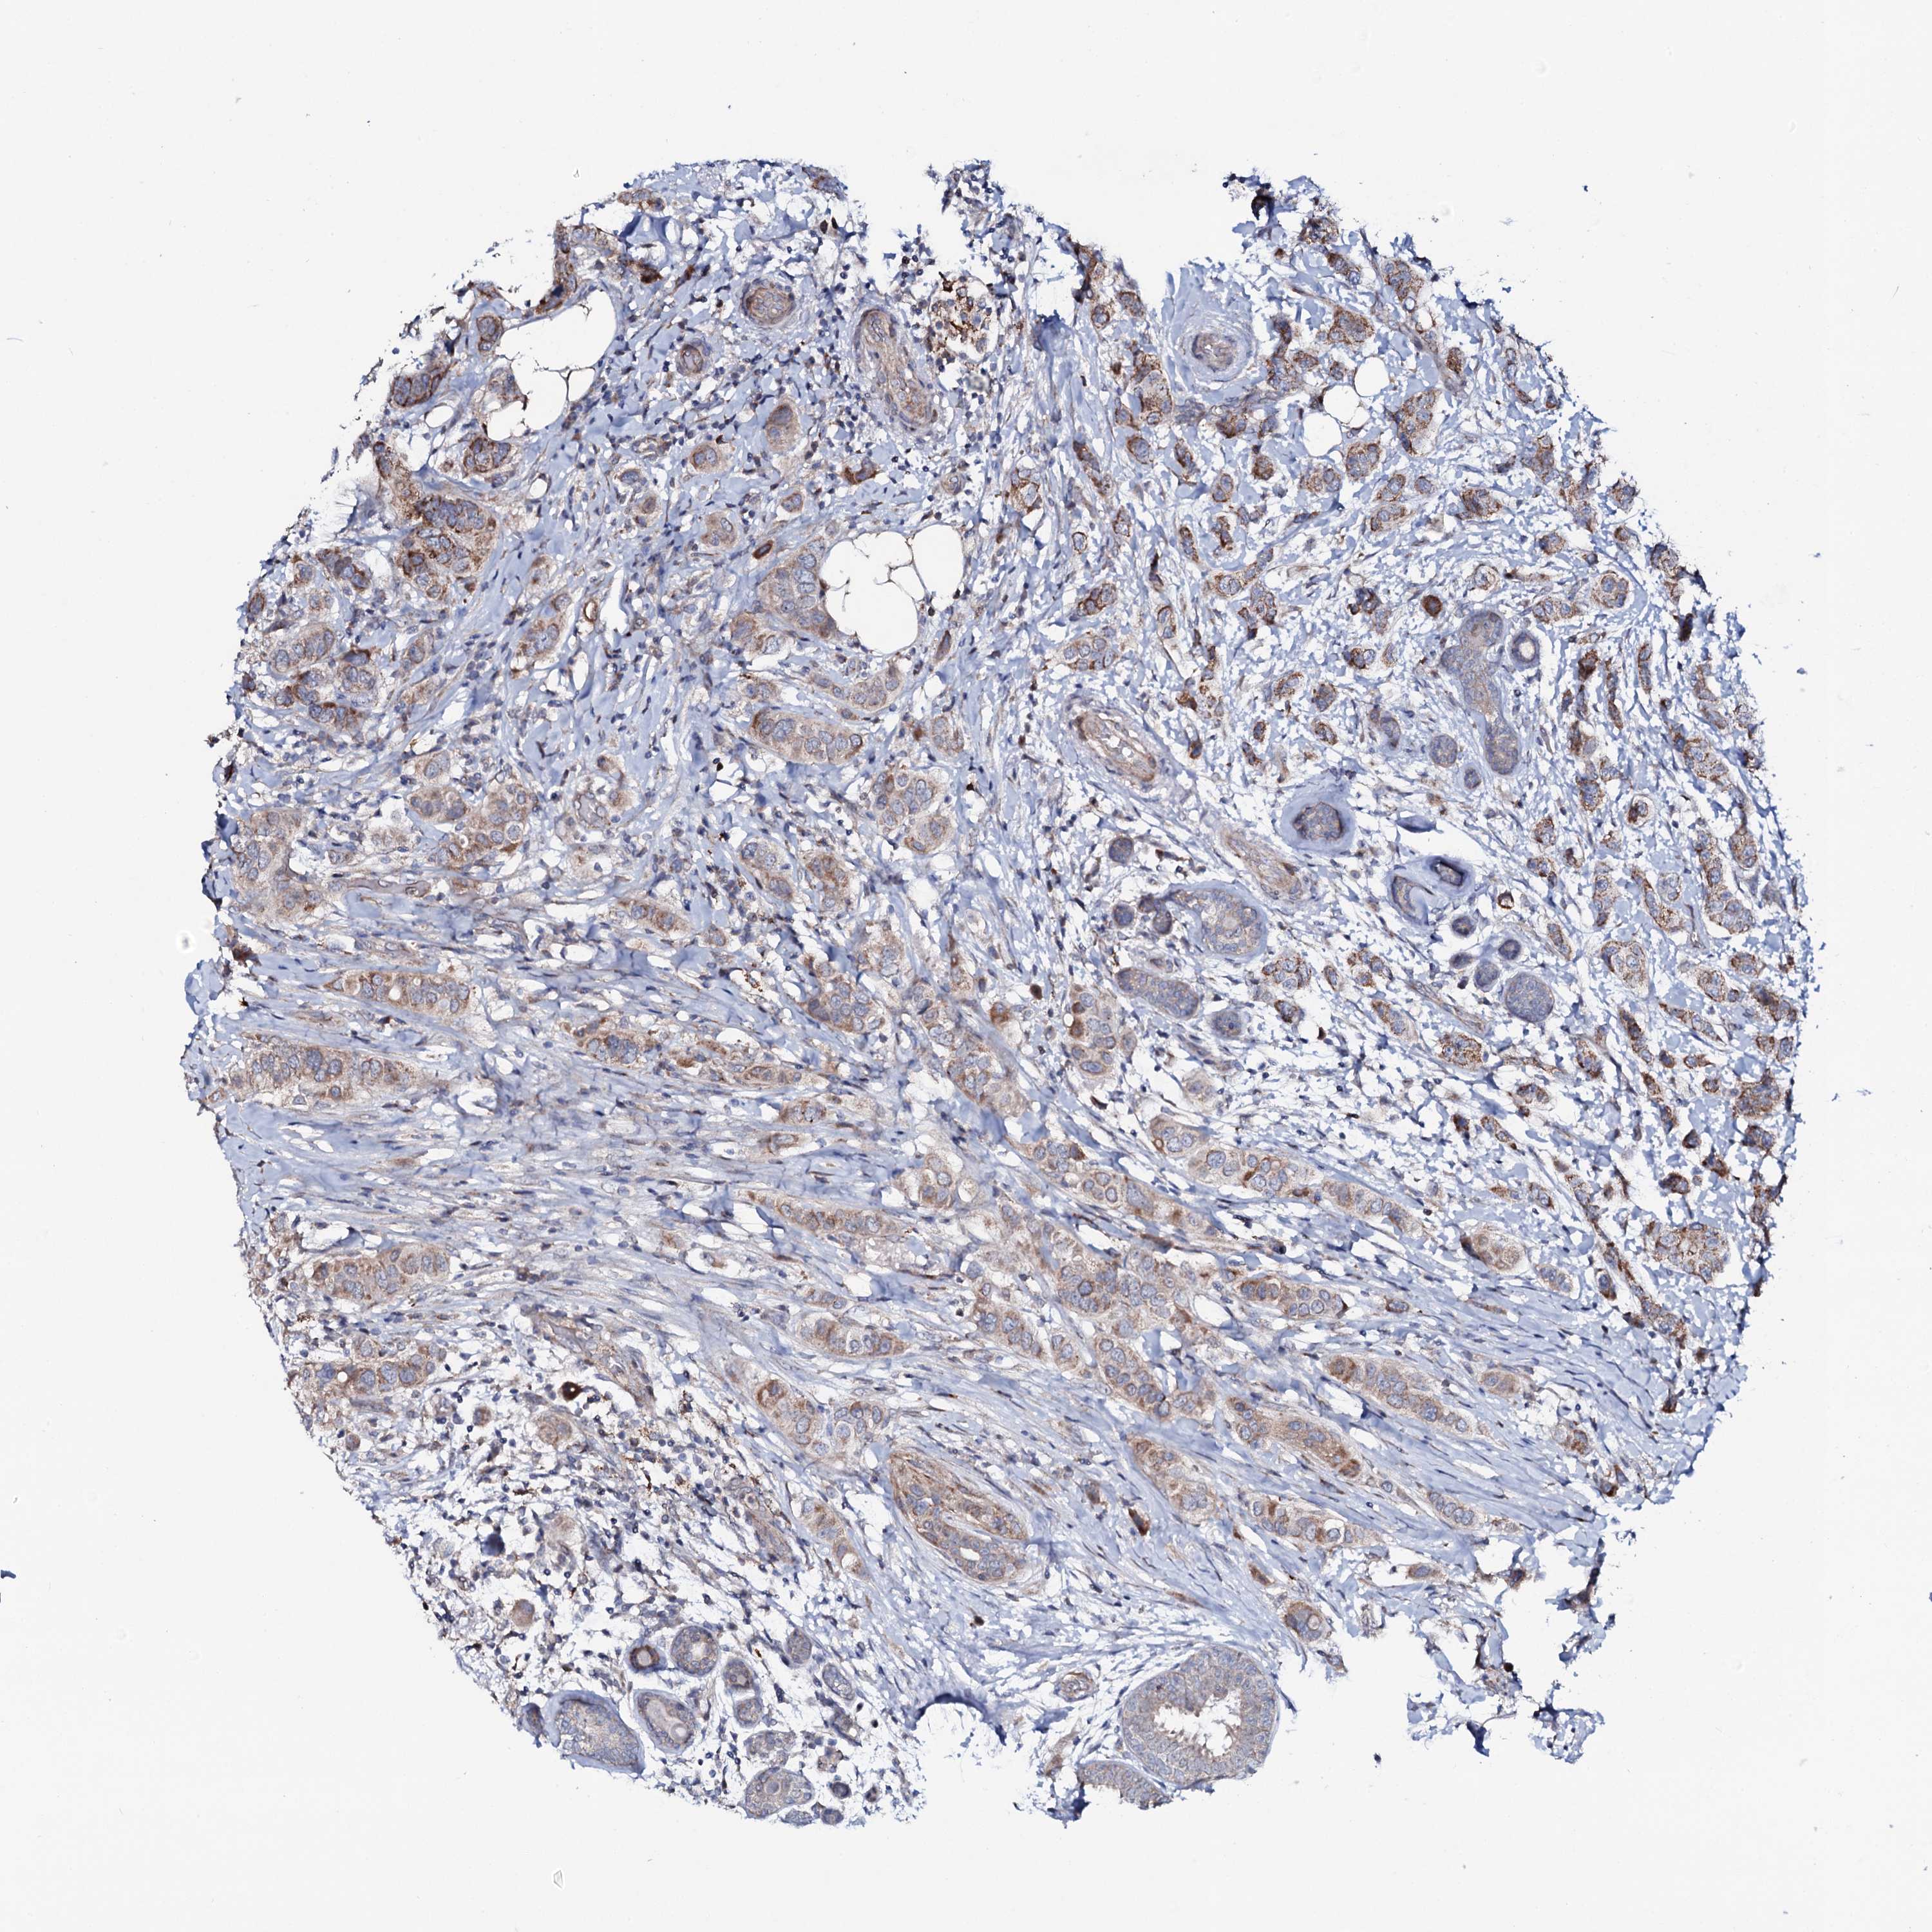

CANCER BREAST CANCER Show tissue menu

BRCA TCGA BRCA VALIDATION PROTEIN EXPRESSION

Breast cancer

Human cancer

Breast invasive carcinoma